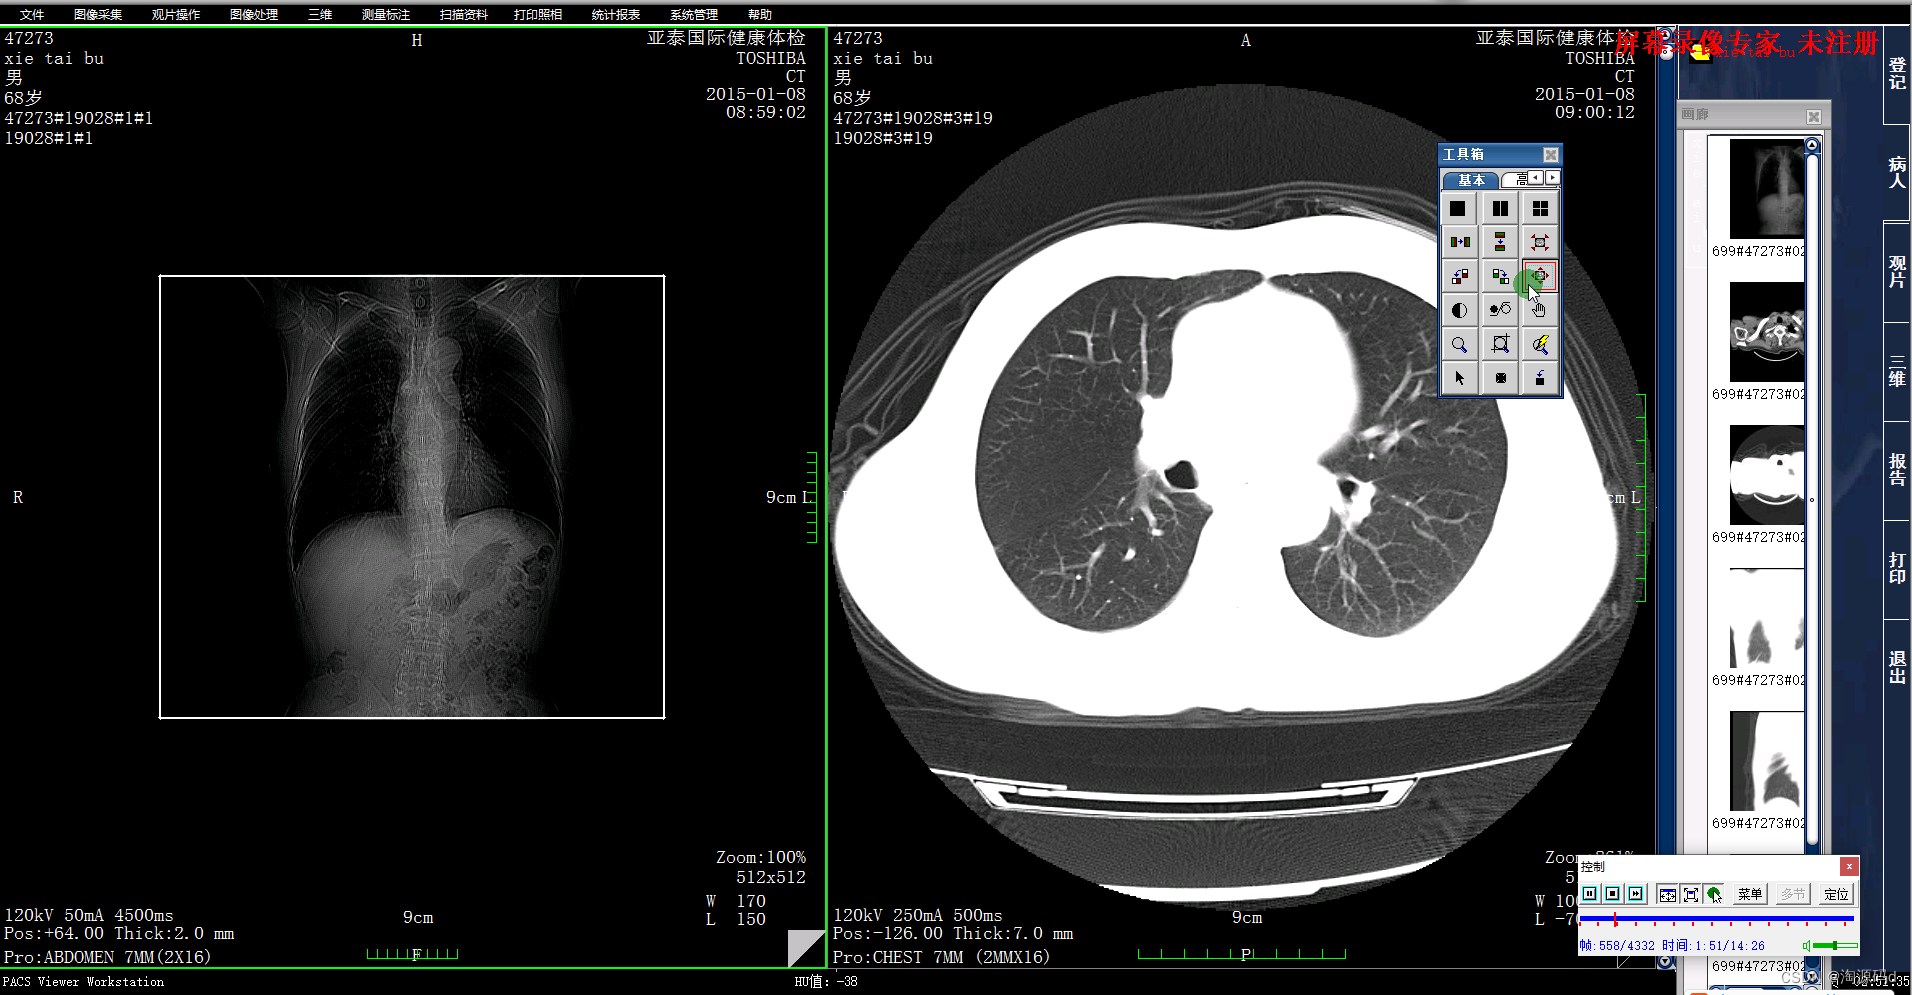

图像浏览及3D后处理系统

图像显示

亮度/对比度调节,窗宽/窗位调节;

单幅/多幅显示,同步操作;

缩放、局部放大;

图像移动、旋转、镜像、反像显示。

测量标注

CT值测量;

长度、角度、矩形、椭圆、曲线任意面积测量;

自定义显示DICOM标注信息;

定位线显示。